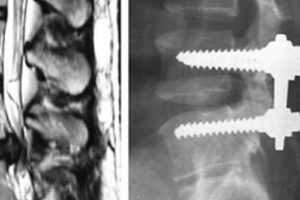

Нове відкриття спінальної хірургії

Унікальна методика спінальної хірургії успішно впроваджена в клініки Ізраїлю. Медичні працівники лікарні Меїр стали учасниками реалізації патенту на імплантати Titanium Chip. Можливості спінальної хірургії Нова технологія операції на спині …